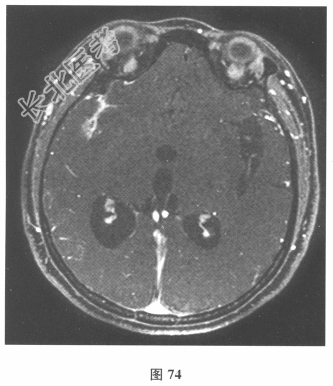

患者入院后复查腰椎穿刺:脑脊液抗酸染色(-),墨汁染色(-),嗜酸性粒细胞比例增高,淋巴细胞体积较大。血及脑脊液弓形虫抗体均(-),血及脑脊液囊虫IgG抗体均(+),莱姆病抗体(-)。追问病史,曾经食用过“米猪肉”。进一步行颅脑MRI检查见图74、图75。)根据上述患者病史和检查结果,对此患者下一步治疗的药物包括